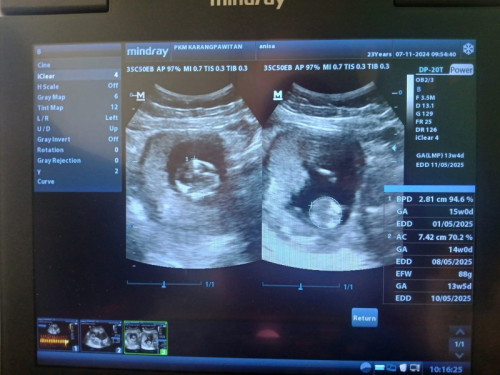

Perkiraan usia kehamilan (GA). Kalo yg di tabel biru kanan bawah itu berdasar ukuran bayinya sekarang (ukuran tulang pelipis kiri dan kanan, lingkar perut, dll), sedangkn yang tulisannya GA (LMP) yg atasnya tabel itu yg berdasar hpht. Kalo haidnya teratur, biasanya yg dijadikan patokan usia kehamilan berdasar hpht. Kalo yg berdasar ukuran bayinya itu untuk memastikan kalo bayinya tumbuh sesuai usia. Biasanya di akhir usg dokternya bakal menyimpulkan “ini usia kehamilannya sekitar 14-15 minggu”. CMIIW

Baca lagiGA atas HPHT , GA bawah sesuai ukuran janin usg kak . Kalau akusih lebih milih ikutin HPHT

Kayanya itungan hpht sm usg beda ya bun, GA nya beda beda.